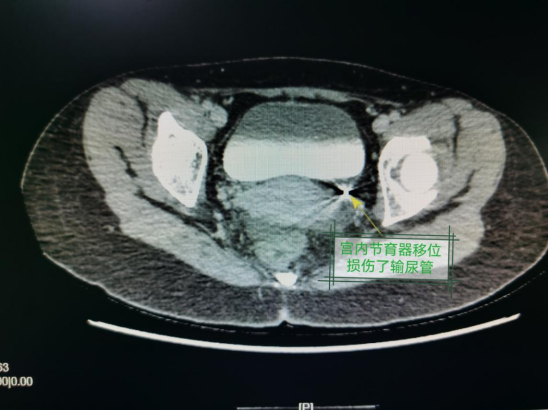

荆楚网(湖北日报网)讯(记者 毛易媛 通讯员 江泓颖 陈舒)38岁的杨女士家住孝感,一个月前突然出现漏尿症状,且据其描述该症状跟活动与否无关。为此,她不得不使用尿不湿,这已经严重影响她的工作、生活及睡眠。一周前,杨女士前往当地多家医院门诊就诊,治疗效果不佳。“到底是什么原因导致自己尿液外流呢?”带着心中的疑问,杨女士决定前往武汉市第三医院继续就诊。武汉市第三医院泌尿外科主任杨军为张女士完善了泌尿系增强CT、B超等相关检查,结合检查,考虑她为左侧输尿管狭窄伴左肾积水、宫内节育器移位、双子宫畸形。

“女士是畸形子宫,左右两侧子宫都安装了节育环,杨女士漏尿可能与左侧宫内节育器移位损伤左侧输尿管致输尿管子宫瘘有关。需要手术取出宫内节育器。”尿外科主任杨军说。于是,泌尿外科杨军主任赶紧联系了妇科罗芳主任一起进行诊断,事实证实了他的推测。

于是泌尿外科杨军主任、周舰副主任医师、王潇主治医师联合妇科罗芳主任医师团队对患者的病情进行了团队联合讨论,反复讨论手术中可能出现的问题,并制订了详细的手术方案。6月15日,两个科室联合成功的为患者进行了手术。先在腹腔镜监控下通过宫腔镜检查子宫内的具体情况,找到节育环嵌顿的位置,取出嵌顿的节育器,再在腹腔镜下完成输尿管损伤部位上方切断并结扎,在膀胱顶壁重新“开个小洞”并与“健康”的输尿管缝合,即输尿管膀胱再植术,彻底解决了患者漏尿的问题。